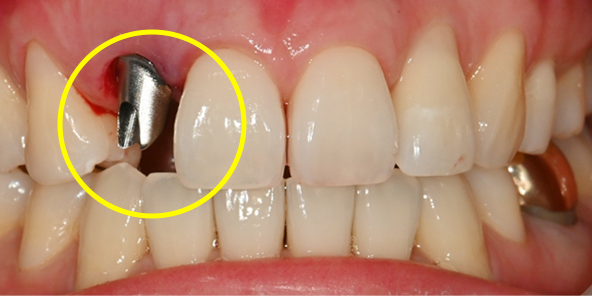

하루 완성 임플란트 가능한 조건

수술할 부위 치아 주변의 치주골 손상이 적은 경우

발치하는 치아 뿌리 끝 주변의 잇몸뼈가 튼튼한 경우

식립할 부위에 뼈의 양이 충분한 경우

발치 및 식립 부위에 염증이 적거나 거의 없는 경우

하루 완성 임플란트는 환자분의 잇몸뼈 상태에 따라

수술 가능 여부가 결정됩니다.